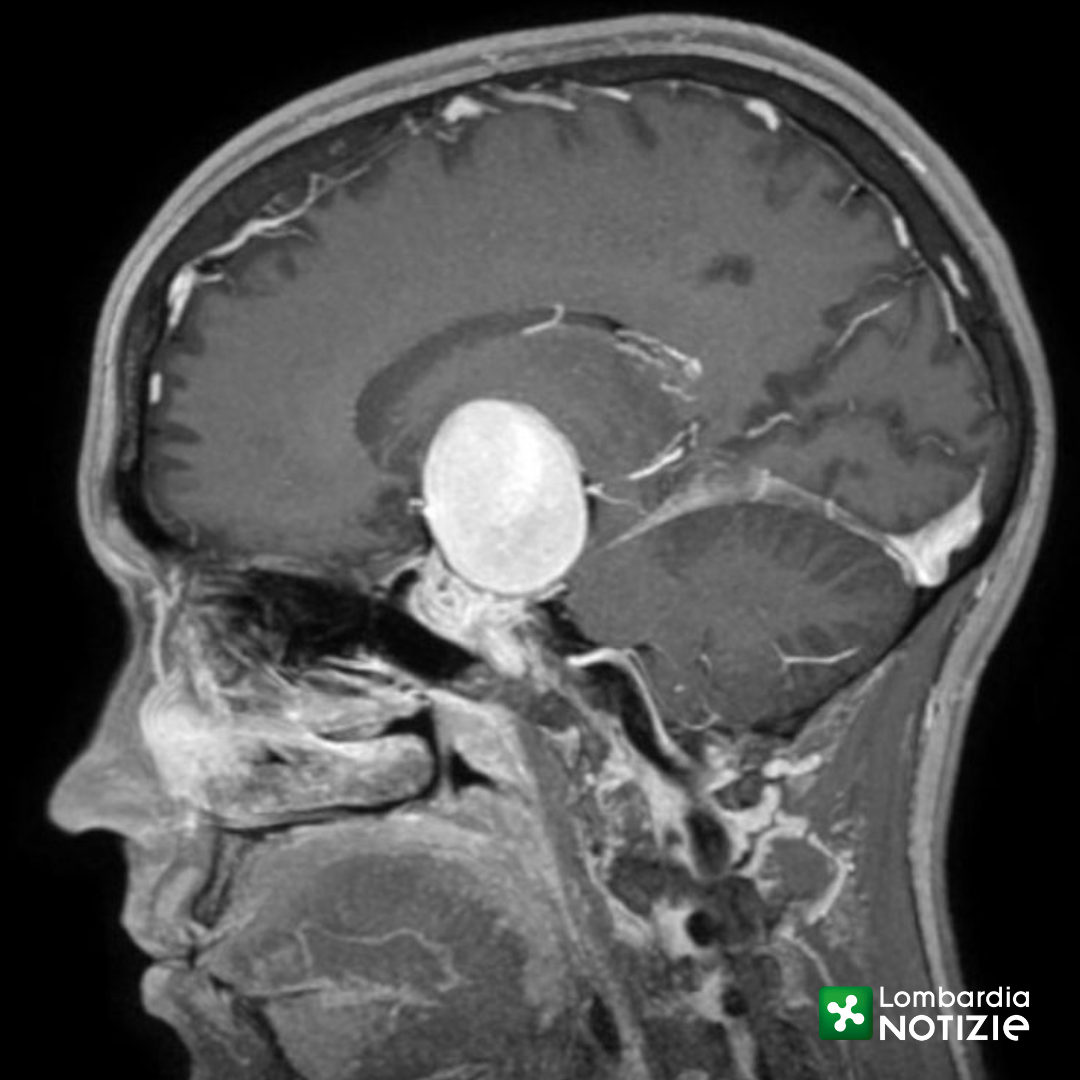

Scopre all’improvviso un aneurisma gigante nel cervello 24enne veneta salvata con un intervento chirurgico eccezionale all’ospedale di Niguarda.

Una forte cefalea e la scoperta di avere un aneurisma cerebrale “gigante” con un rischio di rottura altissimo: così cambia completamente la vita Anna (nome di fantasia), una giovane ragazza di 24 anni che, improvvisamente, si viene a trovare in una condizione di concreto e imminente pericolo di morte.

Aneurisma di 4 cm dell’arteria carotide interna al cervello

“L’aneurisma cerebrale è una patologia acquisita nella quale la parete di un arteria cerebrale si sfianca e forma un «palloncino» che rischia di esplodere. In questo caso si trattava di un rigonfiamento dell’arteria carotide interna del diametro di ben 4 cm (gli aneurismi vengono definiti «giganti» sopra i 2,5 cm)” – spiega Marco Cenzato, Direttore della Neurochirurgia. “Spesso gli aneurismi rimangono silenti oppure vengono riscontrati in maniera accidentale durante esami diagnostici per altre problematiche. Quando si manifestano è perché stanno diventando instabili e il rischio di rottura è altissimo, con esito, purtroppo, spesso letale”.